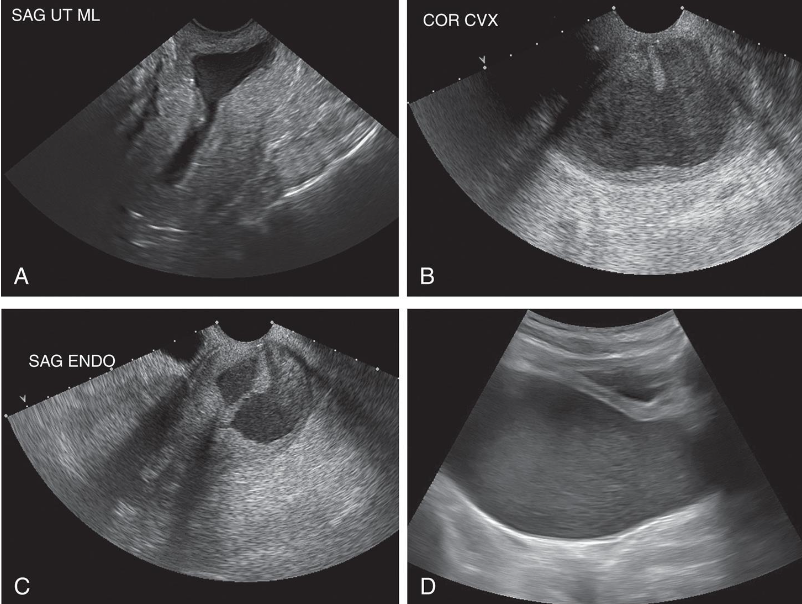

• Cervical stenosis is acquired condition.

• Obstruction of cervical canal at internal or external os resulting

from

• Radiation therapy

• Previous cone biopsy

• Postmenopausal cervical atrophy

• Chronic infection

• Laser or cryosurgery

• Cervical carcinoma

• Menopausal patient may be asymptomatic even though stenosis

can produce a distended, fluid-filled uterus (the result of an

accumulation of uterine secretions, fluid hydrometra, pyometra,

or hematometra).

• Intracavitary fluid collections can be readily seen on ultrasound

and may be indirect indicator of cervical stenosis.

• Premenopausal patients may experience abnormal bleeding,

oligomenorrhea, amenorrhea, cramping, dysmenorrhea, or

infertility.

Cervix Stenosis

• Sonography may demonstrate a solid retrovesical mass, which may be

indistinguishable from a cervical myoma.

• Transvaginal and translabial ultrasound may demonstrate bladder,

ureteral, vaginal, or rectal involvement and may be used in staging

cervical cancer.

• CT and MRI are preferable because they are superior methods for

staging and evaluating lymphatic spread.

• Areas of increased echogenicity or hypoechoic areas with an irregular

outline signify changes compatible with cervical carcinoma.

• Ultrasound is also helpful in guiding biopsies of the cervix and vagina.

• Translabial or transperineal sonography may be used instead of or with

the transvaginal approach to help define the cervical area.